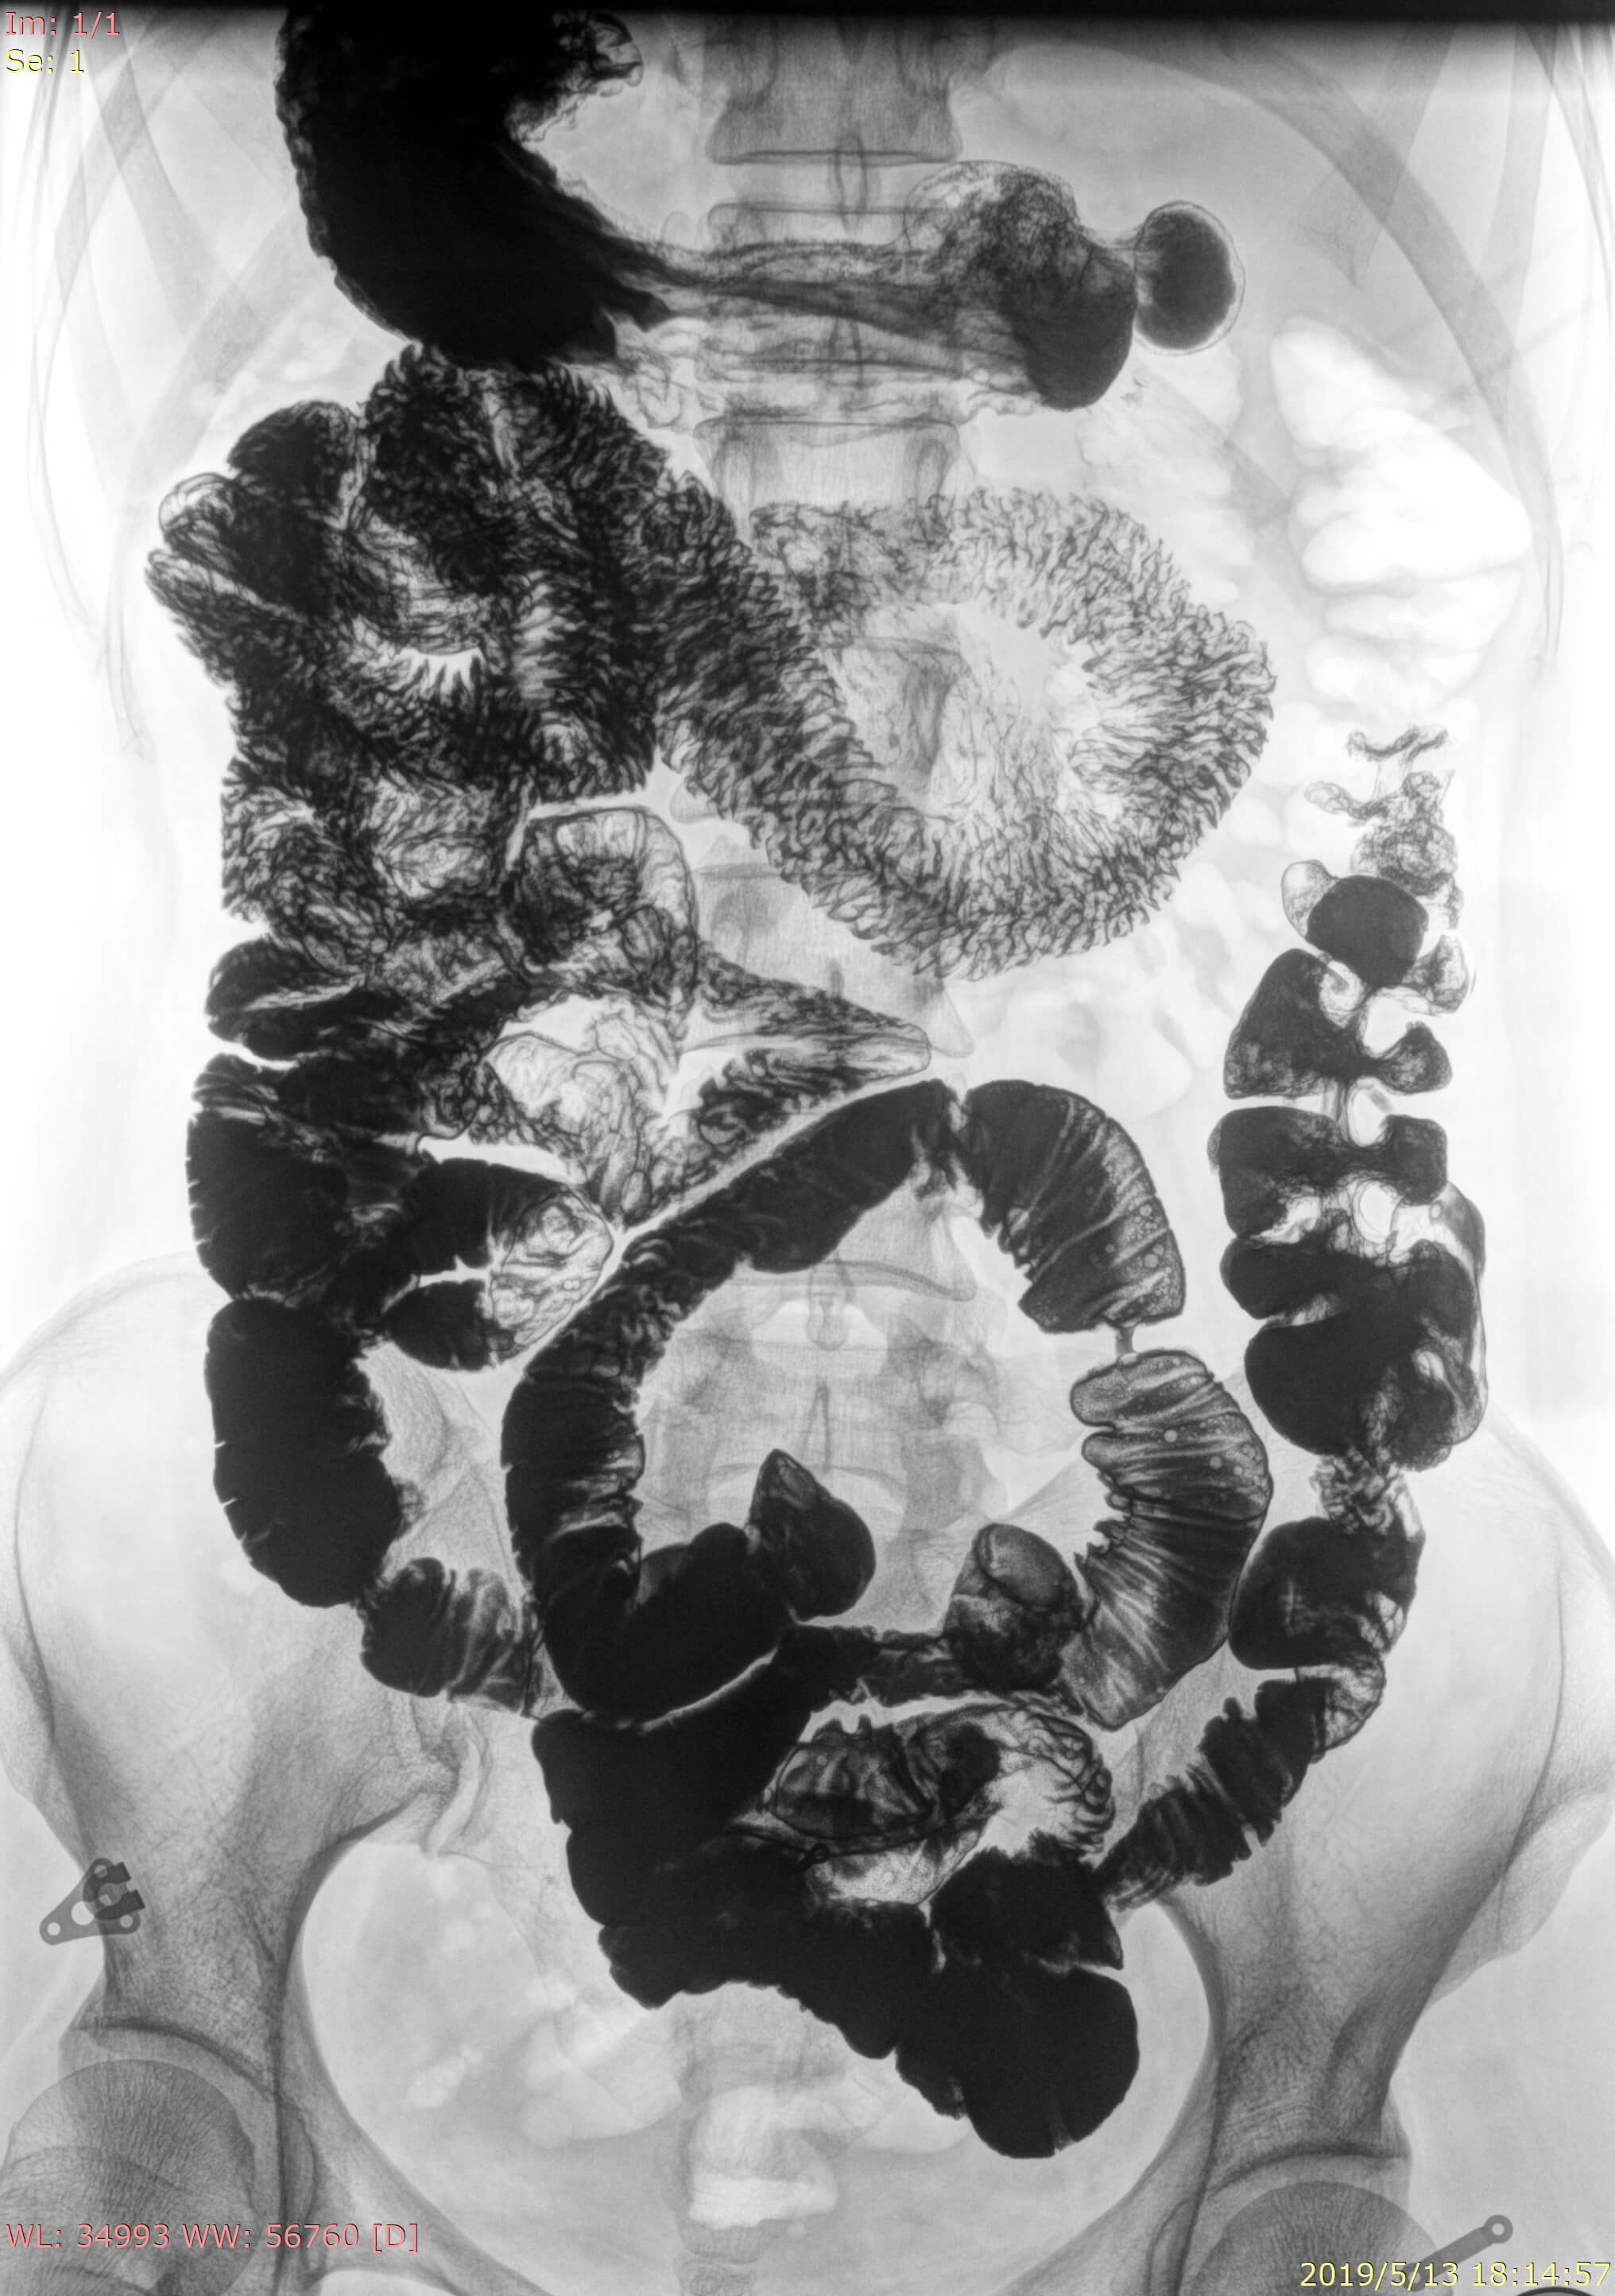

• Wide clinic applications